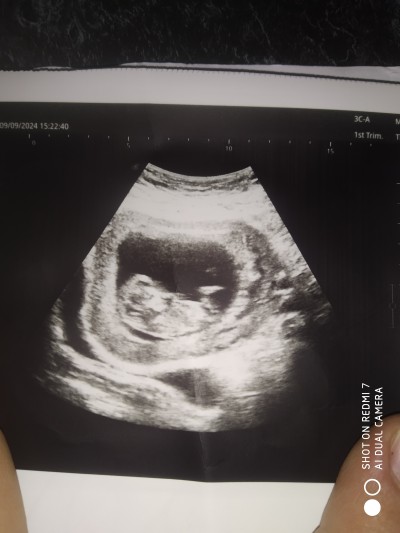

Kızlar daha 11-12 hafta arası. Doktor henuz belli olmaz cinsiyyeti dedi. Ama ikinci kizimda 11haftasinda öyrenmişdim. Qaliba bu doktor iyi bakamadi. Oylesine paylaşıyorum. Siz ne hiss ettiniz? Kız mi erkek mi sizce? Bence kiz

Kafası büyük ve tepesi yassı duruyor, erkek diyorum. Hiç anlamam ben de kendi doktorumun söylediğini söylüyorum. İlk oğlumda bunlara bakıp erken tahmin yapmıştı, şimdi de kızım oluyor onun da kafası yuvarlak ve normal boyutta.